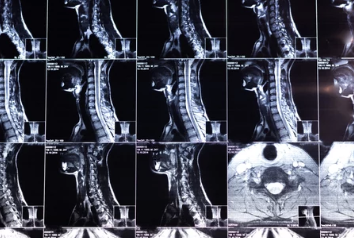

목디스크의 정의

목디스크(경추 추간판 탈출증)는 목뼈 사이에 있는 디스크(추간판)가 탈출하거나 찢어져 신경을 압박하는 상태를 말합니다. 이로 인해 통증, 저림, 움직임 제한 등이 발생합니다.